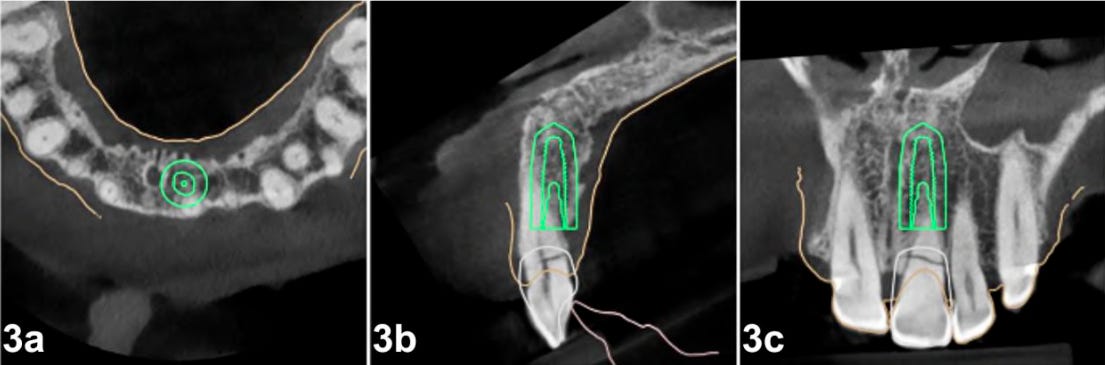

Instalação do Implante: mantendo uma distância de aproximadamente 1,5 mm do escudo vestibular, e buscando a ancoragem mais próxima da parede palatina.

Vamos a um caso clínico que explica muito bem esta abordagem (realizado pela Dra. Juliana Cavalcante Duarte ORCID: https://orcid.org/0000-0001-9630-7717, artigo original disponível neste link):